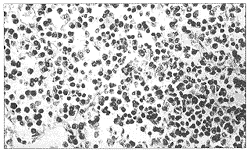

全结肠息肉状浆细胞型淋巴肉瘤1例

短篇及病例报告

患者女性 ......